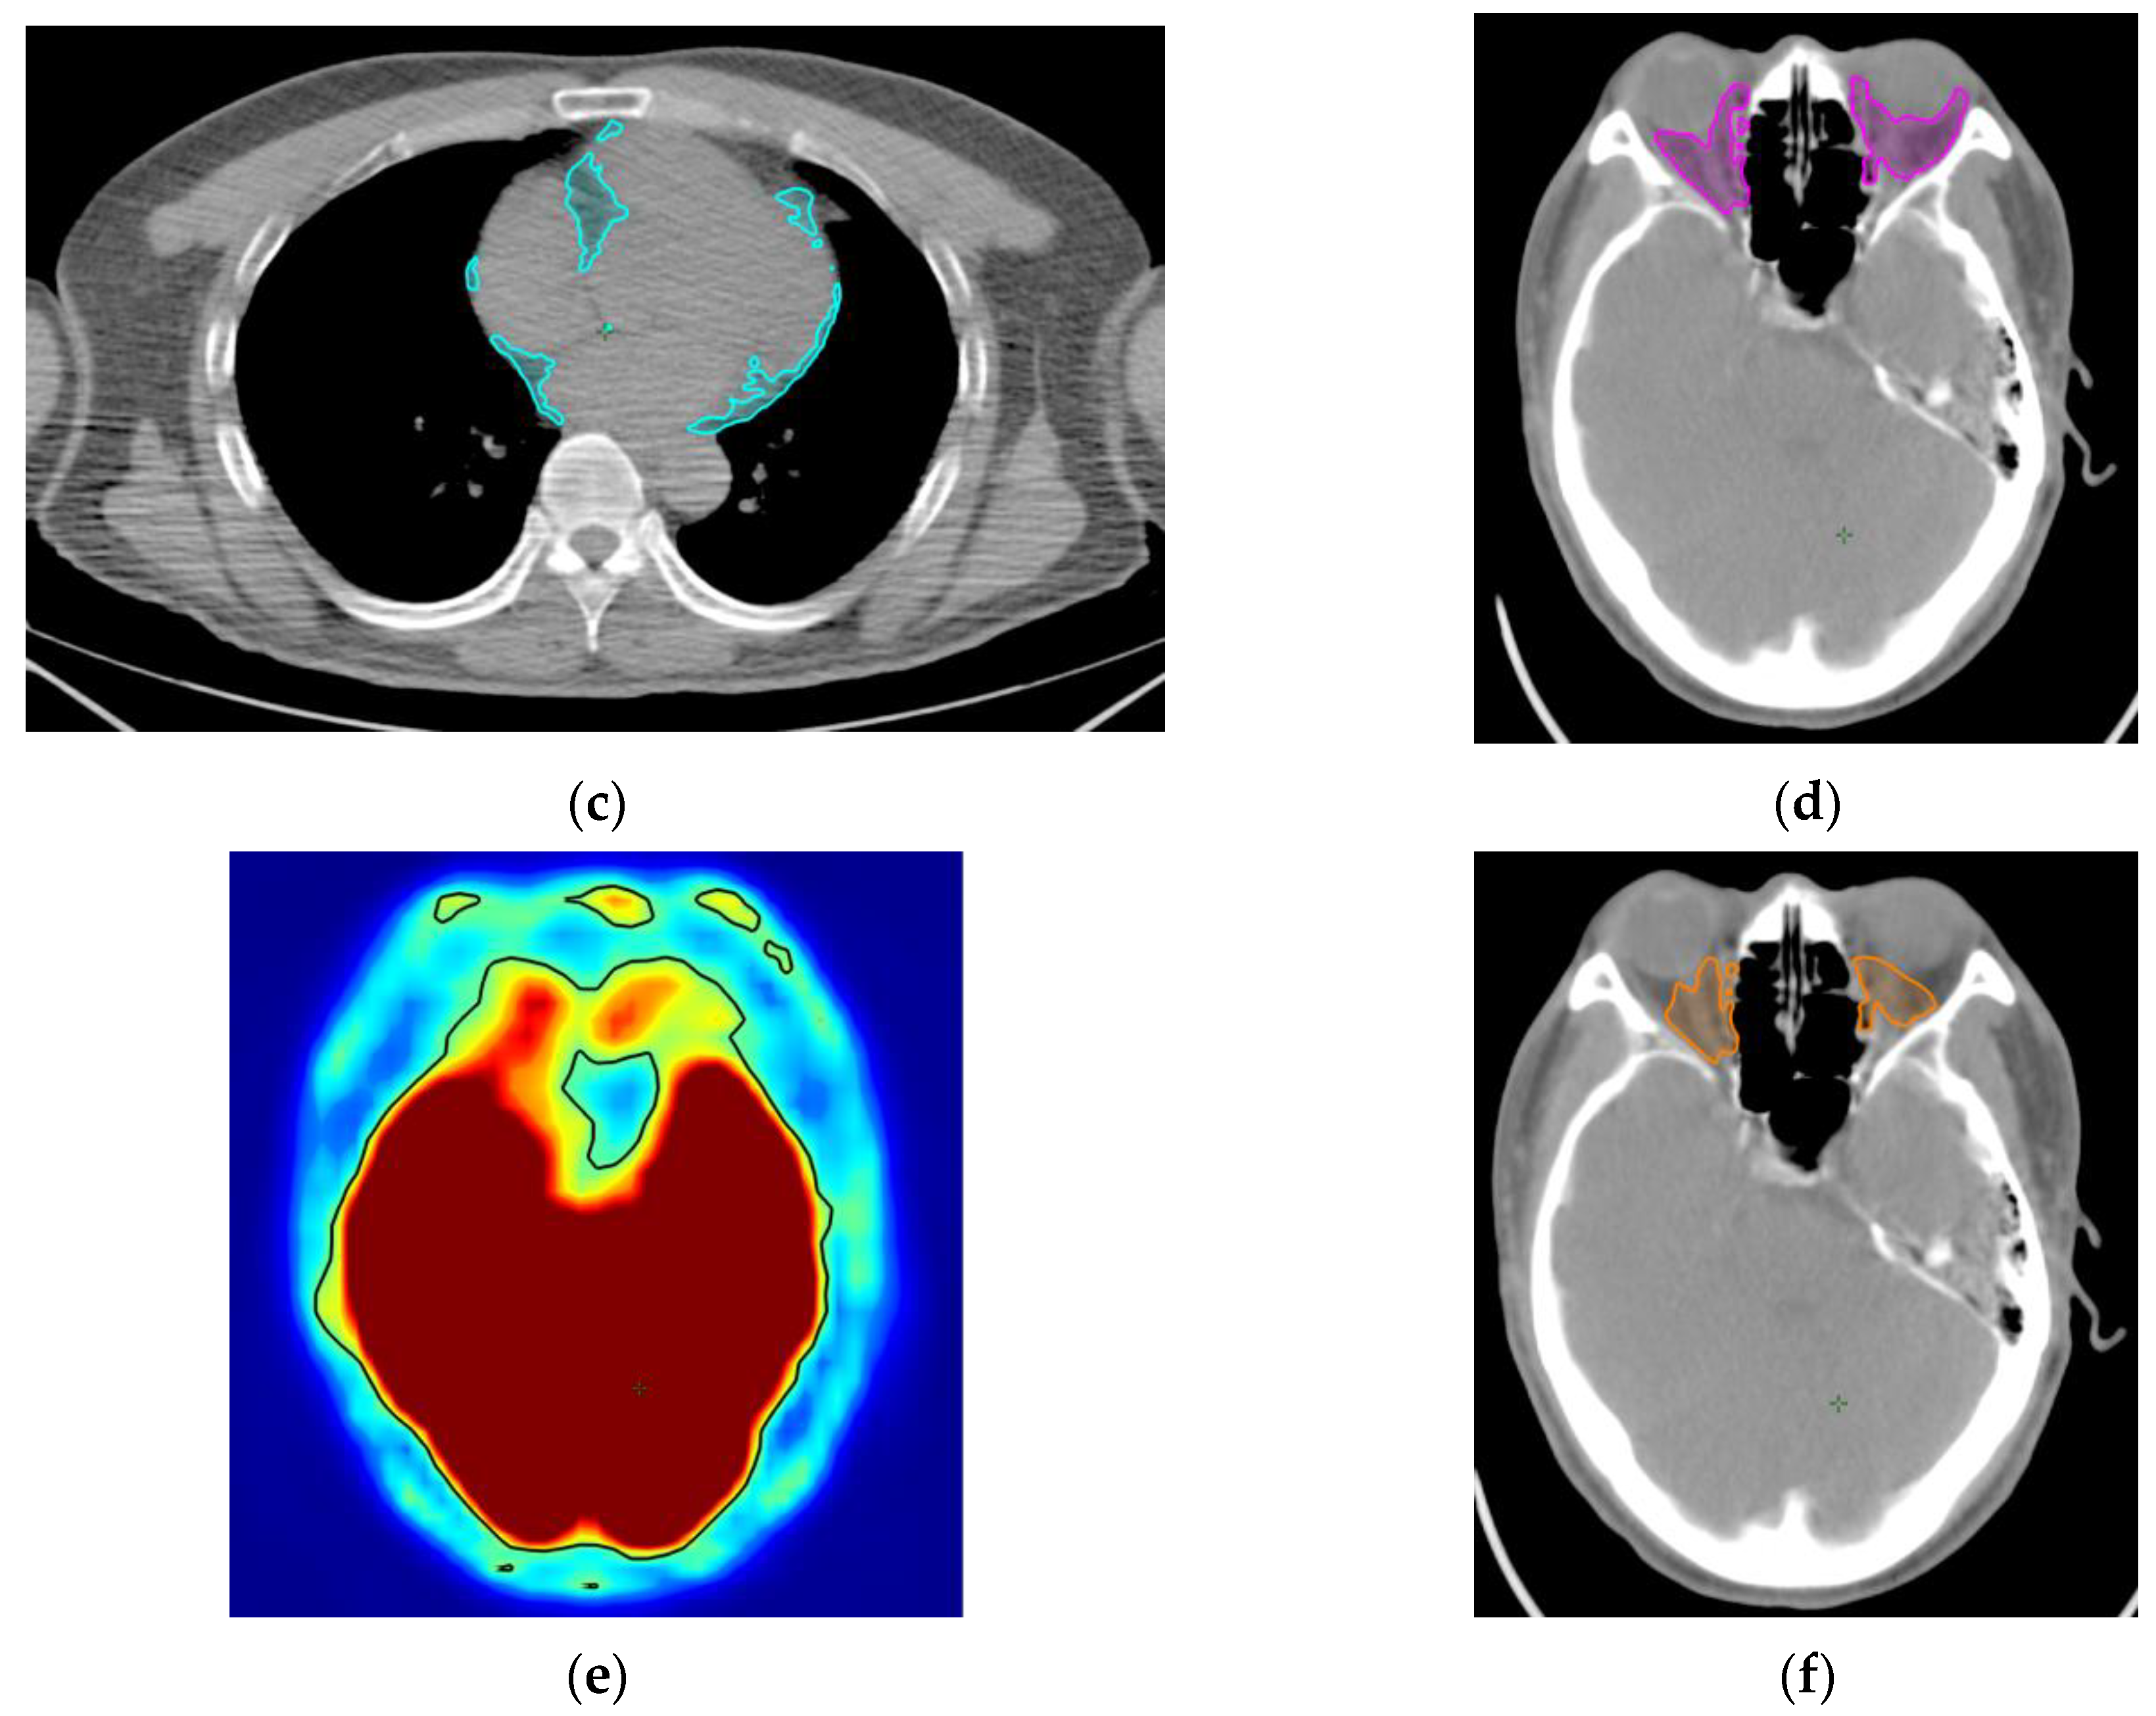

4. Materials and Methods